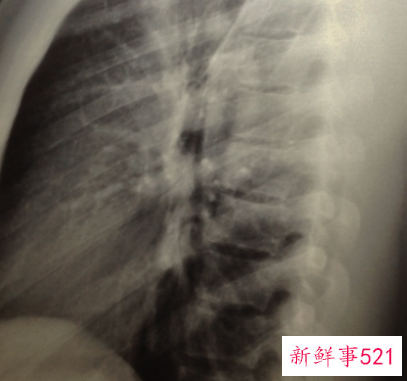

皮肤,可以说是机体最大的器官,而荨麻疹堪称皮肤病中最常见的问题,特别是荨麻疹还可能是机体内部出现问题后的重要提示,所以荨麻疹长期不见好转时,更要做个彻底检查。检查时不必担心X线诱发的问题,一般情况下X线本身不会引起荨麻疹。但做X线时有些情况会使用一些放射线造影剂等药物,这些造影剂可能会偶尔诱发过敏反应,从而出现荨麻疹。

所以,当我们在以前做X线检查使用造影剂中尚未出现过敏,以后再做类似检查时,也不太可能诱发荨麻疹。如果已经知道自己对某种造影剂过敏,同时又必须进行相关X线检查时,可事先告知放射科医生,医生会根据患者的情况,选择其他造影剂。

皮肤是身体最大的器官,如果皮肤有病症将会给患者带来无穷伤害,有的人在做了X光照检查的时候出现了荨麻疹,一般来说单纯的X光是不会引起荨麻疹发生的,但是在做X光的时候需要用到一些放射线造影剂等类的药物,这些造影剂可能会造成过敏反应,导致了荨麻疹的发生,如果以前做过X光检查没有发生过荨麻疹,那以后再做X光检查的时候也不必担心会发生荨麻很,如果之前做X光检查的时候有过荨麻疹的发生,以后就减少做X光检查,必须做X光检查的时候应该提前告知医生,医生会根据你的情况选择其他的造影剂。